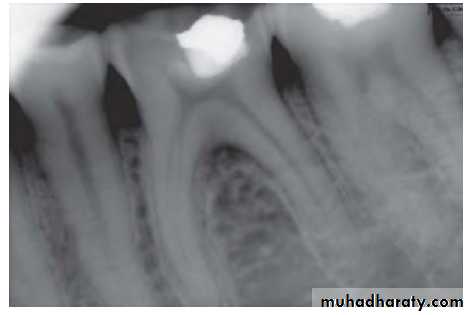

2. Radiographic findings:

– May show depth and extent of caries.– Periapical area shows normal appearance but a slight widening may be evident in advanced stages of pulpitis.